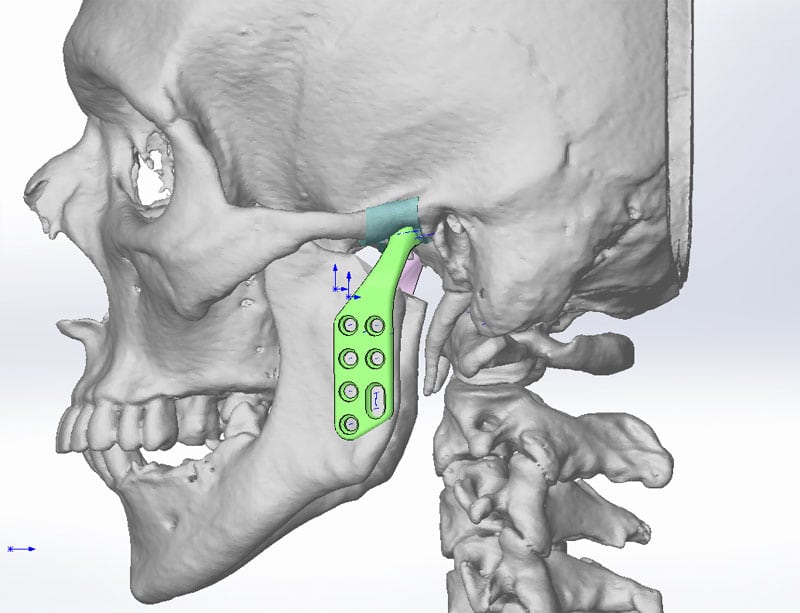

- хирургическое вмешательство. При проведении операции может быть удален сустав, устранена или пересажена головка нижней челюсти, установлен имплантат.